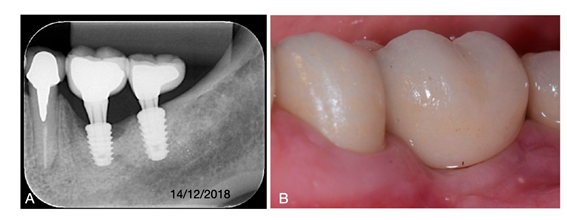

Uma paciente de 54 anos, não fumante, com boas condições de saúde geral, perda de dentes por doença periodontal, e relatando acompanhamento com periodontista privado. Foram realizadas cirurgia mucogengival para aumento de mucosa queratinizada e reabilitação com implantes nas regiões de 36 e 3. Porém, após 2 anos, ela retornou com queixa no implante 36, relato de eventualmente “inchaço”, e no momento com dor e sangramento durante a higiene. No exame clínico foi percebido aumento discreto de volume, secreção, sangramento e profundidade de sondagem aumentada e medindo 10 mm na proximal mesial, 9 mm na proximal distal, 7 mm vestibular, e também 7 mm na lingual. A radiografia periapical, associado aos sintomas e sinais clínicos, indicaram o diagnóstico peri-implantite (Fig. 1a-b). O tratamento proposto foi primeiramente remover a coroa e irrigação local com clorexidina 0,12% e colocar um parafuso cobertura por 4 semanas, com objetivo de fechamento espontâneo da mucosa. Após esse período, foi realizado retalho para exposição do implante, preservando papilas e evitando margem das coroas adjascentes reabilitadas a pouco mais de 2 anos. O debridamento foi realizado com curetas periodontais padrão Gracey Mini-Five 11/12 e 13/14, além de pontas Piezoelétricas para descontaminar e promover sangramento no osso adjacente. Para descontaminação química na superfície do implante, foram utilizados ácido fosfórico 37% por 3min., irrigação com sol. Salina 0,9%, seguido de EDTA 24% (Prefigel) por 2 min., seguido novamente por irrigação sol. salina 0,9% (Fig. 2a-c). Apesar da perda óssea, devido às características morfológicas do defeito, foi realizado procedimento regenerativo para reconstrução do defeito residual. Com a finalidade de manter espaço para regeneração óssea, foi colocado um cicatrizador de 3.5 mm diâmetro x 1.5 mm de altura. A superfície do implante foi umedecida com matriz derivada do esmalte (Endogain). Em seguida, o defeito foi preenchido com osso bovino agregado em colágeno (Extra Graft), e coberto por dupla camada de membrana, sendo a última com endogain aplicado antes da sutura (Fig. 3a-d). O implante permaneceu submerso na mucosa por 5 meses. Após esse período, foi realizado reabertura minimamente invasiva com instalação de coroa provisória feito com pilar temporário (Fig. 4a-b). A coroa temporária permaneceu por mais de 1 ano. Somente após esse período, sem sinais flogísticos e sintomatologia, foi concluída a coroa final. A imagem periapical após 18 meses, e o aspecto clínico com 19 meses, após a reabertura com provisório, demonstram que dentro desse período de proservação o implante se apresenta com saúde e estabilidade tecidual, sugerindo sucesso na proposta terapêutica aplicada (Fig. 5a-b).